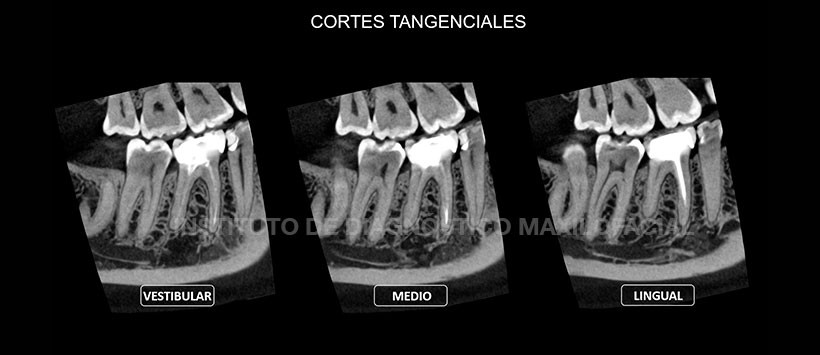

En los cortes axiales (Figura 2), transaxiales y tangenciales (Figura 3 y Figura 4) de la tomografía volumétrica de haz cónico se pueden apreciar la presencia de cuatro conductos (dos conductos en la raíz mesial y dos en la distal), los cuales están obturados a excepción del conducto distolingual. Así mismo dicho conducto presenta una obliteración a nivel del tercio inferior en zona apical.